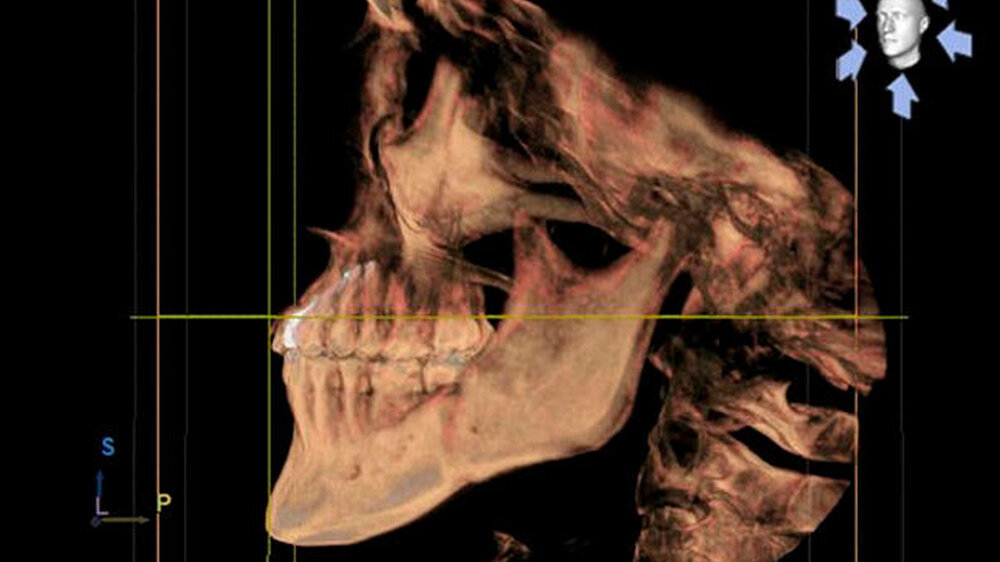

Eine 20-jährige Patientin stellte sich erstmalig zur Implantat- und Distraktionsberatung in unserer Abteilung für Mund-, Kiefer- und Gesichtschirurgie vor. Diagnostisch lagen eine mandibuläre Retrognathie, retinierte und verlagerte Zähne 18, 28, 38 und 48, ein Zapfenzahn 12, ein fehlender Zahn in regio 022, eine Mittellinienverschiebung und ein Engstand der Oberkieferfront vor (Abbildungen 1a bis d). Im Rahmen der klinischen Untersuchung und basierend auf dem Auswertungsergebnis der Digitalen Volumentomografie (DVT) führten wir bei der Patientin im Hinblick möglicher therapeutischer Maßnahmen eine differenzial-therapeutische Beratung durch.

Klinisch als auch radiologisch lag eine konvergierende Wurzelstellung der Zähne 21 und 23 vor. Eine unkomplizierte implantatprothetische Versorgung der Lücke 022, das heißt ohne Verletzung der benachbarten angulierten Zähne, erschien nicht möglich. Die Schwierigkeit bestand darin, die Lücke 022 durch körperliche Bewegung der Zähne zu öffnen, was sich bislang mittels festsitzender Apparatur als frustran erwiesen hatte. Der Patientin wurde aufgrund der vorliegenden Diagnose eine parodontal akzelerierte osteogenetische Orthodontie (PAOO) im Bereich des linken Oberkiefers empfohlen.

Fallbezogen stellte sich die PAAO wie folgt dar: Vestibuläre paramarginale Schnittführung von regio 14 nach regio 24 des Oberkiefers sowie palatinal etwa 2 mm unterhalb des Gingivalsaums. Subperiostale Präparation eines Mukoperiostlappens. Vertikale und horizontale Kortikotomie mit dem Mectron- PiezonSurgery® Gerät aller Zahnfächer.

Des Weiteren erfolgten kortikale Punktbohrungen und die Entnahme eines knöchernen Kortikalis-Dreiecks im Bereich des linken Oberkiefers. Unter Schonung des Nervus inzisivus wurde eine entsprechende Kortikotomie ebenso palatinal angewandt. Dann erfolgte die Auffüllung des vestibulären und palatinalen subperiostalen Raums der Kortikotomiespalten mit Eigenblut getränktem synthetischen Knochenersatzmaterial NanoBone®. Für den abschließenden speicheldichten Wundverschluss wurde monophiles Nahtmaterial 5-0 verwendet.